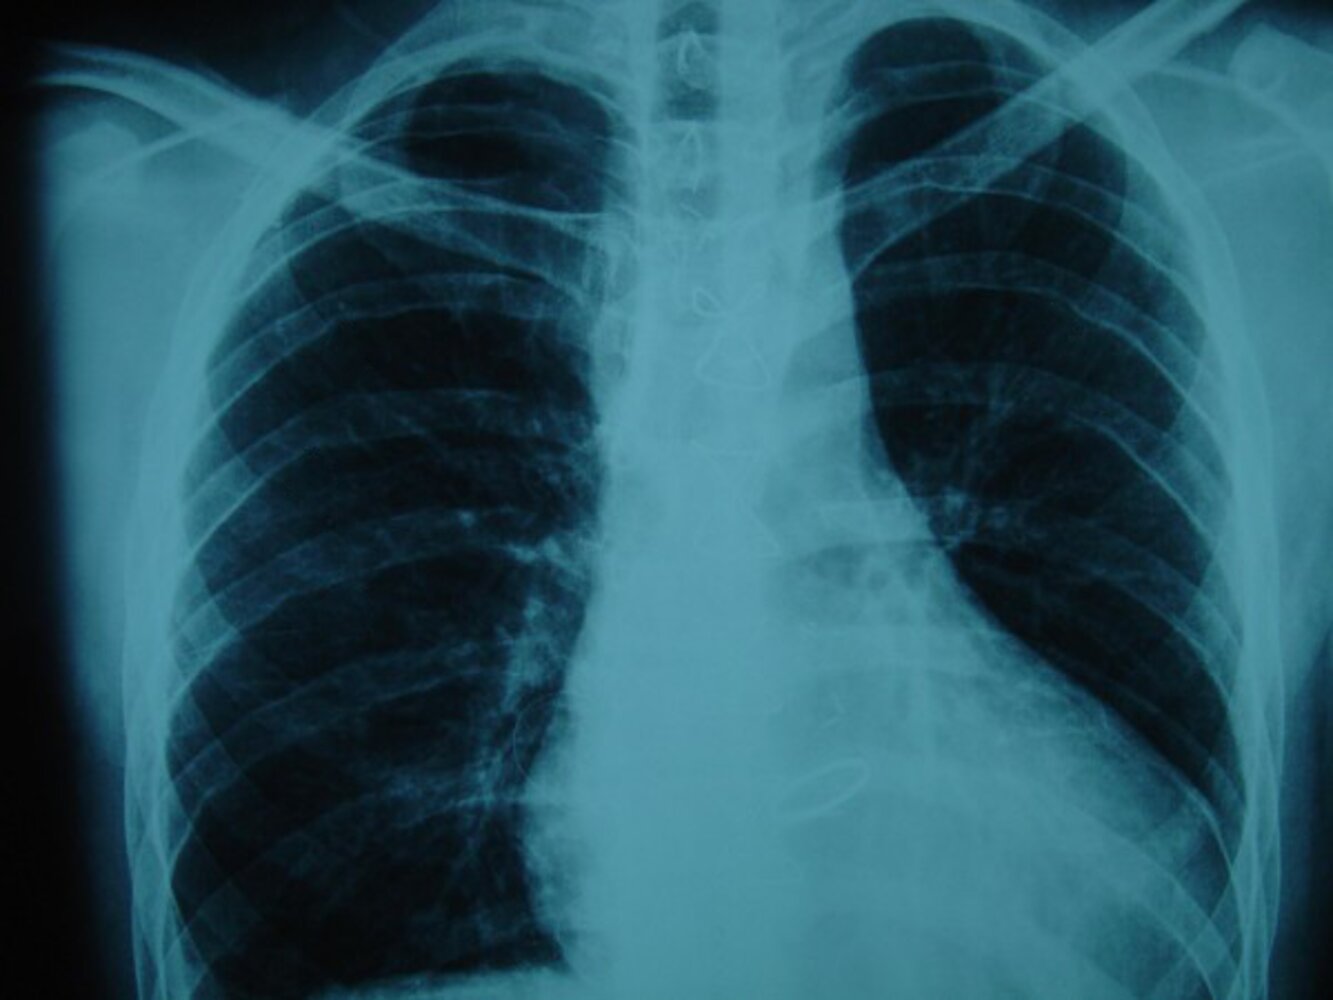

Chest x-ray

- Rounding of the left heart contour due to an enlarged right atrium, right ventricle, and pulmonary artery

- Enlarged lung markings due to enhanced pulmonary vasculature